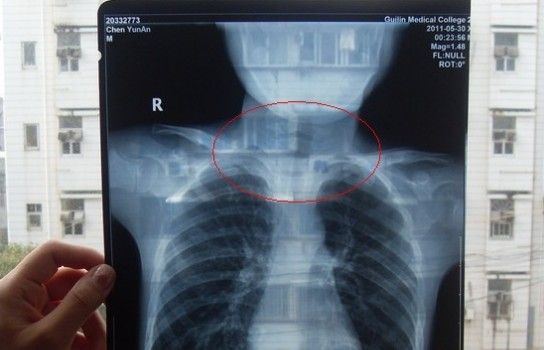

胸部正位X光片圖

2011年5月29日下午,陳先生的兒子安安出現(xiàn)嘔吐、肚子疼痛等癥狀。陳先生立即將兒子送往醫(yī)學院附院,根據(jù)醫(yī)生開出的會診單,分別對安安做了腹部立臥位2次和胸部正位1次共3次X光片檢查、診斷。醫(yī)生看X光片后排除了腸梗阻病因,判斷是闌尾炎。經(jīng)過治療,不久安安身體痊愈。

可是,陳先生的一次偶然發(fā)現(xiàn),讓他們一家過上了提心吊膽的日子。因為,在安安出院一個月后,陳先生偶然翻出孩子治療期間的X光片。發(fā)現(xiàn)在X光片中,孩子的生殖器官以及甲狀腺等敏感部位也在被放射區(qū)域中。而陳先生上網(wǎng)查到:人體拍攝X光片是有一定輻射的,并且輻射有可能引起基因變異等問題,他立馬陷入恐慌中。